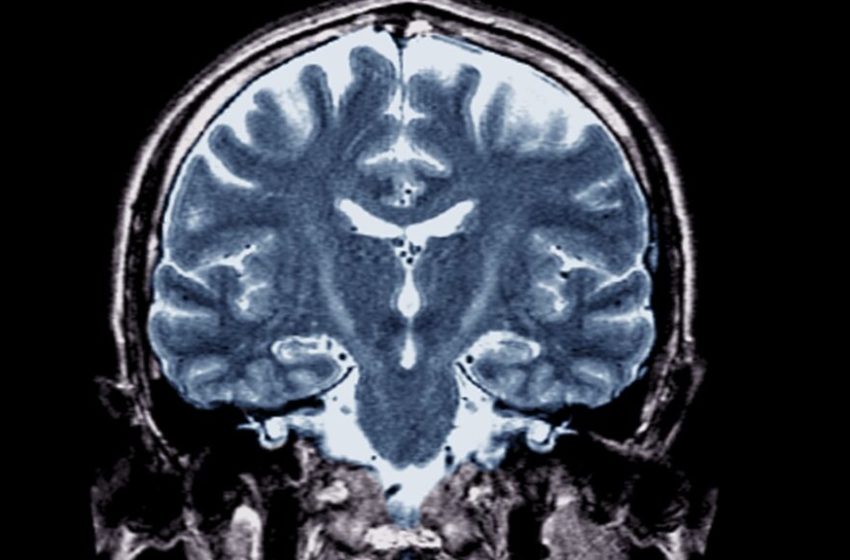

In 2018, when my mom was dying of the fatal neurodegenerative disease amyotrophic lateral sclerosis (ALS), I learned that I carried the same mutated gene, C9orf72, that caused her disease. That means I will likely either develop ALS or frontotemporal degeneration (FTD), another disease that is caused by the C9 mutation.